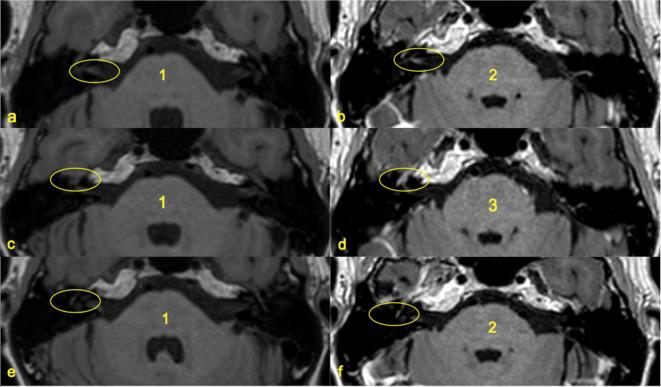

Enhancement patterns of the normal facial nerve on three-dimensional T1W fast spin echo MRI.

Pre- and post-gadolinium 3D T1W fast spin echo imaging studies ( = 64) were retrospectively analysed in patients without suspected facial nerve pathology. Two independent observers scored the signal at each of six skull base facial nerve segments. Wilcoxon signed-rank test was used to compare changes in signal between pre- and post-gadolinium sequences at each location, and how this differed between proprietary sequences or between the pairs of facial nerves.

There was significant enhancement at the fundal canalicular (16%), geniculate ganglion (96%), tympanic (45%) and mastoid (38%) facial nerve segments ( < 0.05). Two different proprietary sequences demonstrated similar patterns of enhancement and there was symmetry between the two sides.